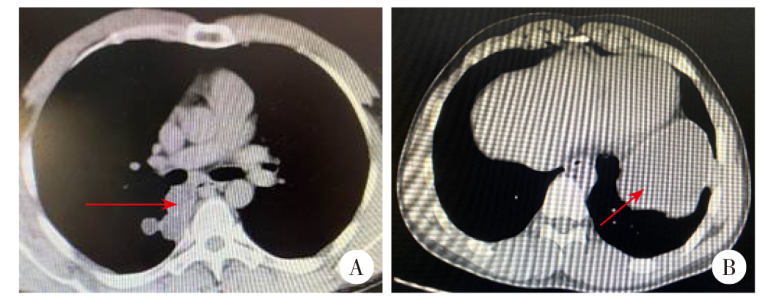

收集2000年1月至2025年4月就诊于新疆医科大学第一附属医院接受手术治疗的21例原发胸膜腔棘球蚴病病例,以描述性流行病学方法对病例进行分析,包括一般资料、流行病学资料、临床表现、胸部CT检查、治疗和转归等。结果显示,病例中男性14例,女性7例;平均年龄为44.8岁。有流行区旅居史或犬类接触史者11例。21例病例中,右侧胸膜腔棘球蚴15例,体检时发现14例,多发棘球蚴15例,有肝棘球蚴病史19例。胸腔镜手术病例6例,开胸手术16例。术后出现肺部感染8例,气胸2例,脓胸1例。术后常规病理检查结果为细粒棘球蚴病16例,为多房棘球蚴病5例。出院后失访4例,随访36个月17例,其中2例分别于术后12个月及15个月复发,15例未见复发。结果提示原发于胸膜腔的寄生虫病术前胸部CT是最佳的检查选择,胸腔镜切除术经过专业评估后对部分患者可能是可行和安全的治疗策略。

The medical records of 21 patients with primary echinococcosis in the pleural cavity that received surgical treatment in the First Affiliated Hospital of Xinjiang Medical University from January 2000 to April 2025 were retrospectively collected, and a descriptive epidemiological method was employed to analyze the demographic features, epidemiological characteristics, clinical manifestations, chest CT scans, treatment and outcomes. The case series included 14 men and 7 women and had a mean age of 44.8 years. There were 11 cases with a history of staying in epidemic areas or contact with canines. There were 15 cases with echinococcosis in the right-side pleural cavity, 14 cases identified using physical examinations, 15 cases with multiple hydatid cysts, and 19 cases with a medical history of hepatic echinococcosis. Surgical interventions consisted of thoracoscopic surgery among 6 cases and thoracotomy among 16 cases. Postoperative complications included pulmonary infection (8 cases), pneumothorax (2 cases), and empyema (1 case), and conventional postoperative pathological examinations revealed cystic echinococcosis in 16 cases and alveolar echinococcosis in 5 cases. Of all cases, there were 4 cases lost to the 36-month follow-up after discharge from hospital, and among the 17 cases completing follow-up, there were 2 cases with recurrence 12 and 15 months post-surgery and 15 cases without recurrence. These findings demonstrate that preoperative chest CT scan is the optimal choice for evaluation of parasitic diseases primarily originating from the pleural cavity, and thoracoscopic resection may represent a feasible and safe therapeutic strategy for selected patients following thorough professional assessment.